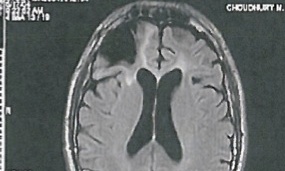

Cecil Clayton’s brain scan shows that he is missing a large chunk of his prefrontal cortex. Photograph: Cecil Clayton

Cecil Clayton, who is scheduled to be executed by the state of Missouri on Tuesday night, is a 21st century Phineas Gage: in 1972, while working in a lumberyard, a malfunctioning saw blade sent a large chip of wood hurling through the air and straight into Cecil Clayton’s skull. He survived but lost 20% of his prefrontal lobe in the accident and everything changed. Whereas once he had a job and a family and was involved in his church, after the accident he became impulsive, suffered from fixed-hallucinations, and had several violent outbursts. One night, in the course of a familial dispute, Clayton shot and killed a police officer that had been dispatched to the scene. A Missouri jury sentenced Clayton to death.

Because of Gage, neuroscientists now know exactly what caused these dramatic personality changes. The iron rod that entered Gage’s skull caused extreme damage to his prefrontal cortex, which is the area of the brain responsible for decision-making. In healthy individuals with a properly functioning brain, the prefrontal cortex helps us to problem solve, abstract from past mistakes and make sound judgments. For individuals like Gage and Clayton, a damaged prefrontal cortex makes it difficult to reign in impulses or to reason through the problems that confront us.